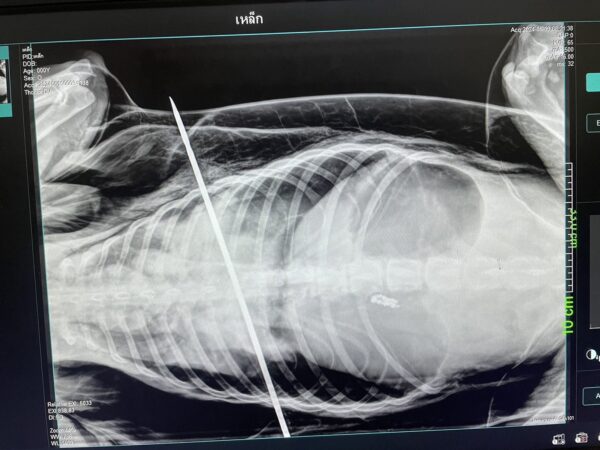

ล่าสุดในช่วงเช้าวันที่ 20 พฤษภาคม 2567 พฤศจิกาได้ลงพื้นที่ไปยังโรงพยาบาลสัตว์ร้อยเอ็ด บริเวณห้าแยกสายน้ำผึ้ง เขตเทศบาลเมืองร้อยเอ็ด แต่แพทย์ผู้ให้การรักษายังไม่ได้เข้าเวร จึงทำการสัมภาษณ์ทางโทรศัพท์ ชื่อเล่นหมออาร์ต (ไม่สะดวกเปิดเผยชื่อจริง)เล่าว่า จากกรณีน้องหมาที่ถูกลูกดอกของหน้าไม้ที่ใช้ยิงปลายิง ยิงเข้าที่บริเวณทรวงอกของน้องหมา ปักทะลุปอด แรกรับน้องมีอาการลิ้นม่วง หายใจเหนื่อยหอบและพบว่าลูกดอกที่ปักจะเด้งตามจังหวะหายใจเอกซเรย์เบื้องต้น ก็พบว่าถูกอวัยวะสำคัญคือปากทะลุปอดและเฉียดหัวใจไปไม่ถึง 3 ซม.